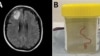

Un gusano de 8 centímetros fue encontrado vivo en el cerebro de una mujer en Australia, y los investigadores dicen que es la primera vez que se descubre este parásito en humanos.